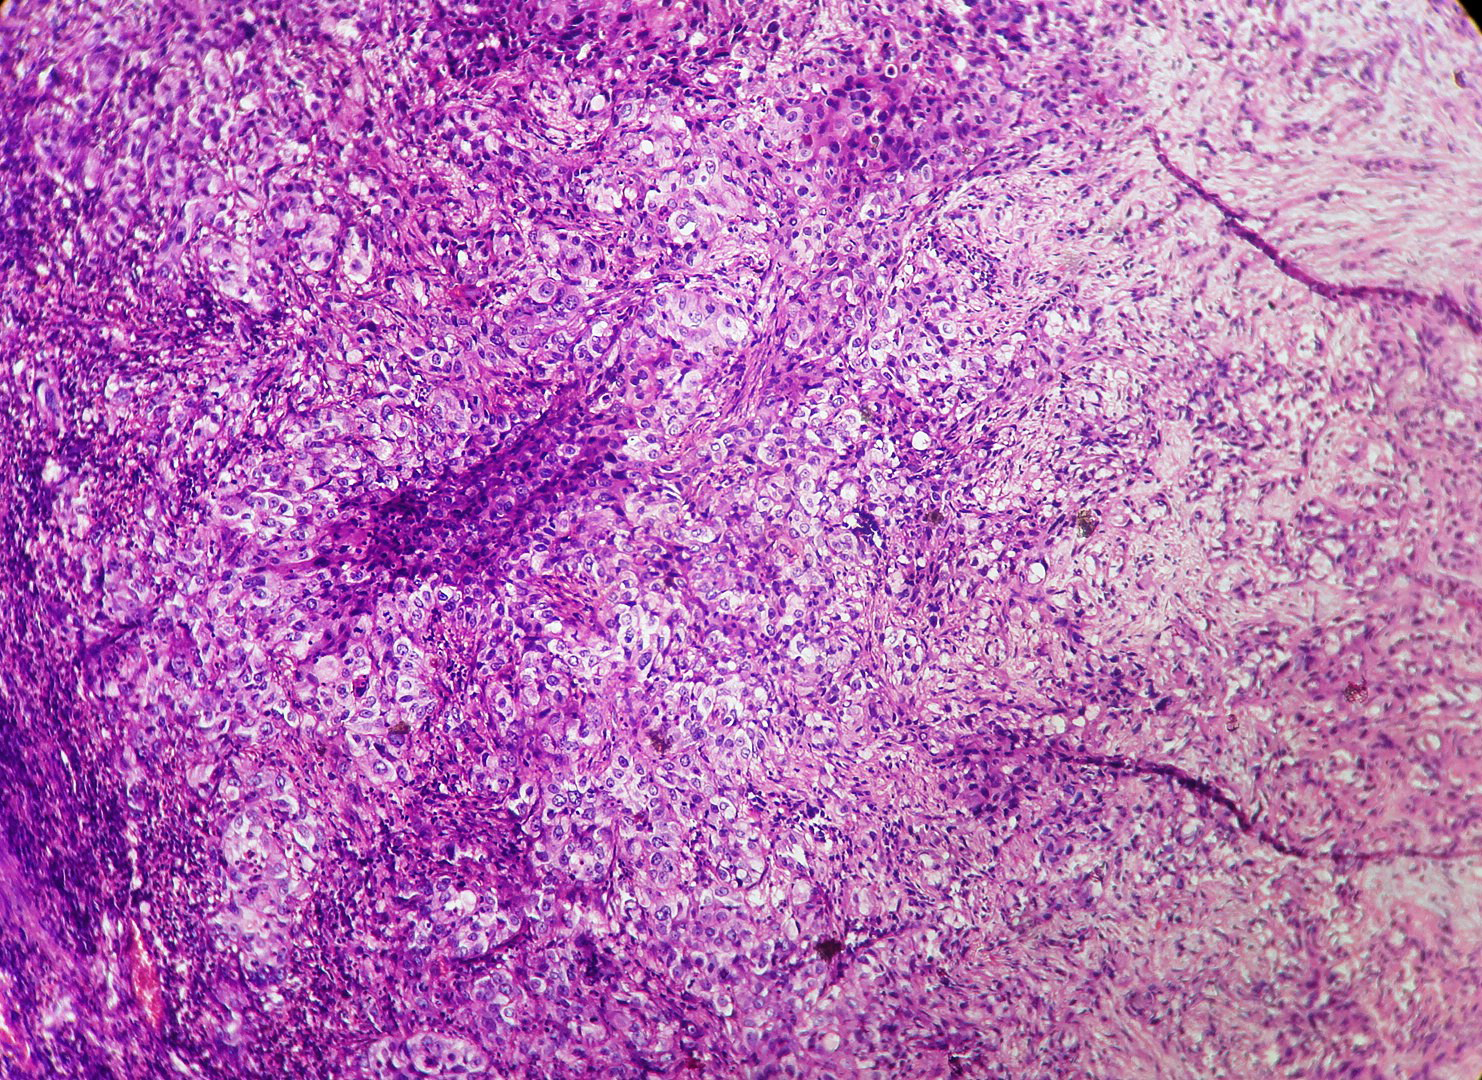

In our study, we made an attempt to evaluate the pattern of tumor growth, its degree of differentiation, progression and associated mucosal changes. In 15 cases of urothelial papilloma, it is characterized by discrete papillary growth with a central fibrovasular core lined by urothelium of normal thickness and cytology (Figure 1). In five cases of Papillary urothelial neoplasm of low grade malignant potential (PUNLMP), histopathologically the tumor is characterized by delicate, orderly, tenuous papillary structures with orderly arrangement of cells within the papillae with minimal architectural abnormalities and nuclear atypia usually limited to basal layer irrespective of cell thickness (Figure 2). The major distinction from papilloma is that in PUNLMP the urothelium is much thicker and nuclei are significantly enlarged. In 21 cases of low grade urothelial carcinoma, histologically it is characterized with papillary axes which are more compact, crowded, fused at the base and lined by unordered cells showing both architectural and cytological abnormalities with frequent mitosis (Figure 3). In 51 cases of high grade urothelial carcinoma showed fused papillary axes over the large areas resulting in sheets and solid areas. The cells have enlarged, hyperchromatic, pleomorphic nucleus in full thickness of the epithelium with increased atypical mitosis (Figure 4). As per TNM staging used in our study we observed majority of the bladder tumours were invasive accounting for 78.25% (Figure 5 & 6) as compared to non-invasive bladder tumours constituting 21.73% of the cases as shown in table 3.

Figure 4 High grade papillary urothelial carcinoma shows tumour cells in sheets and solid areas with marked cellular and nuclear atypia increased mitosis. (H and E stain, 400X).